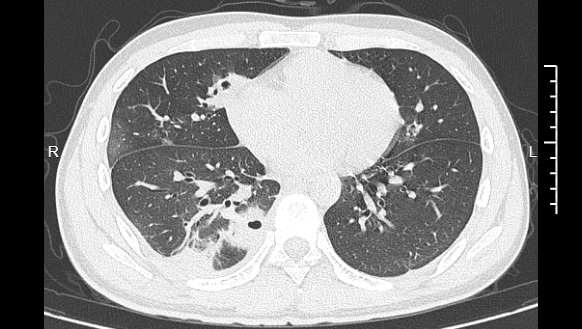

熬到第三天,小林已经烧到39℃,赶紧去医院就诊。接诊的主任医师丁群力一看他的症状,立刻安排了CT检查。结果显示:小林的肺里有十几个空洞,部分肺组织已经坏死,这是典型的血源性肺脓肿。

小林的CT影像显示肺里有多个空洞